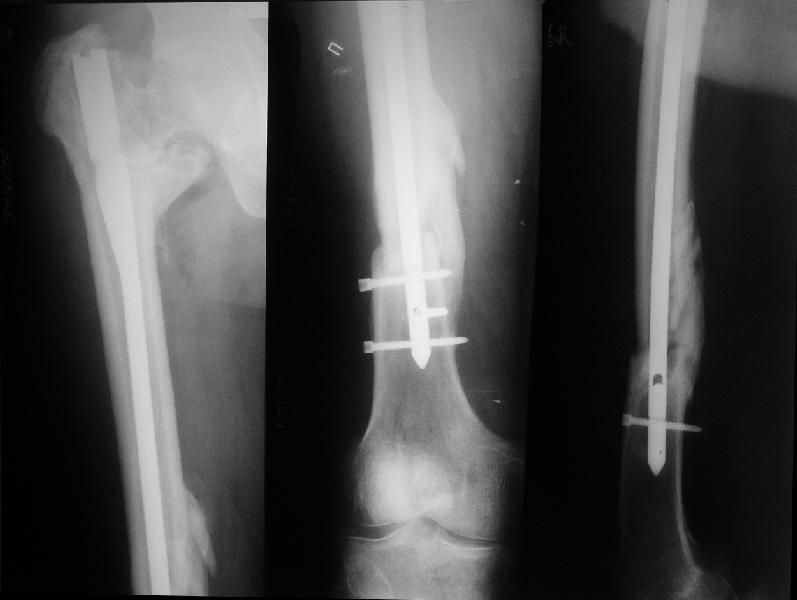

Поскольку в нашем случае выявилась подвижность, мы наложили дистрактор таз-бедро на 3 дня, и сделали остеосинтез гаммой без остеотомии. То, что произошла "корригирующая остеоклазия" в подвертельной области, выявили после введения гвоздя. Пациент уже уехал домой, будем наблюдать.

Секрет успеха в более благоприятной механике, за счет установки линии перелома в более горизонтальное положение. Вальгусная остеотомия создает необходимые механические условия для сращения ложного сустава в шейке и в вертельной области, а также восстанавливает длину конечности. Но любая вальгизирующая операция приведет к неизбежному вальгусу конечности.

Для профилактики вальгуса конечности необходимо создать латерализазацию диафиза, и для быстрейшего сращения необходимо создать компрессию по линии остеотомии.

Интрамедуллярной конструкцией трудно создать все эти условия и поэтому для окончательной фиксации применение 120 или 130 градусной пластины считаю более привлекательным вариантом.